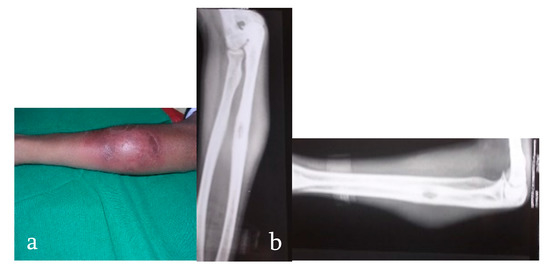

- Stage of early arthritis. Patient presents with joint pain, spasm of the surrounding muscle, and difficulty in doing some activities of daily living. Affected joint has 50–75% of the joint movement preserved. X-ray shows classical Phemister’s triad of juxta-articular osteopenia, mild joint space reduction, and peripheral osseous erosions. This stage has good prognosis with mild stiffness.

- Stage of late arthritis. Patient presents with joint pain, spasm, and difficulty in activities of daily living. Affected joint has >75% loss of range of movement of the joint. X-ray shows marked joint space reduction and joint destruction. This stage has fair prognosis with severe loss of motion.